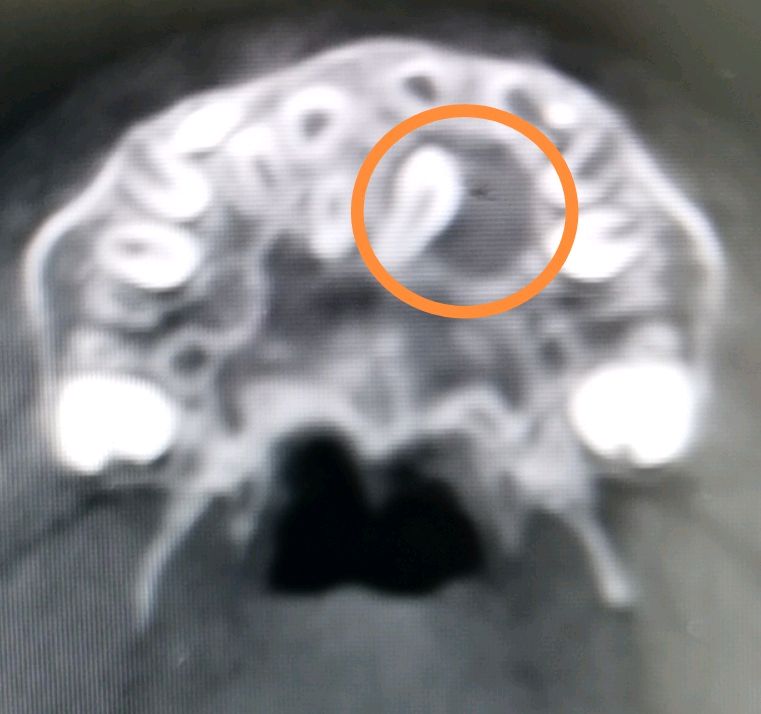

6.多生牙进入鼻腔